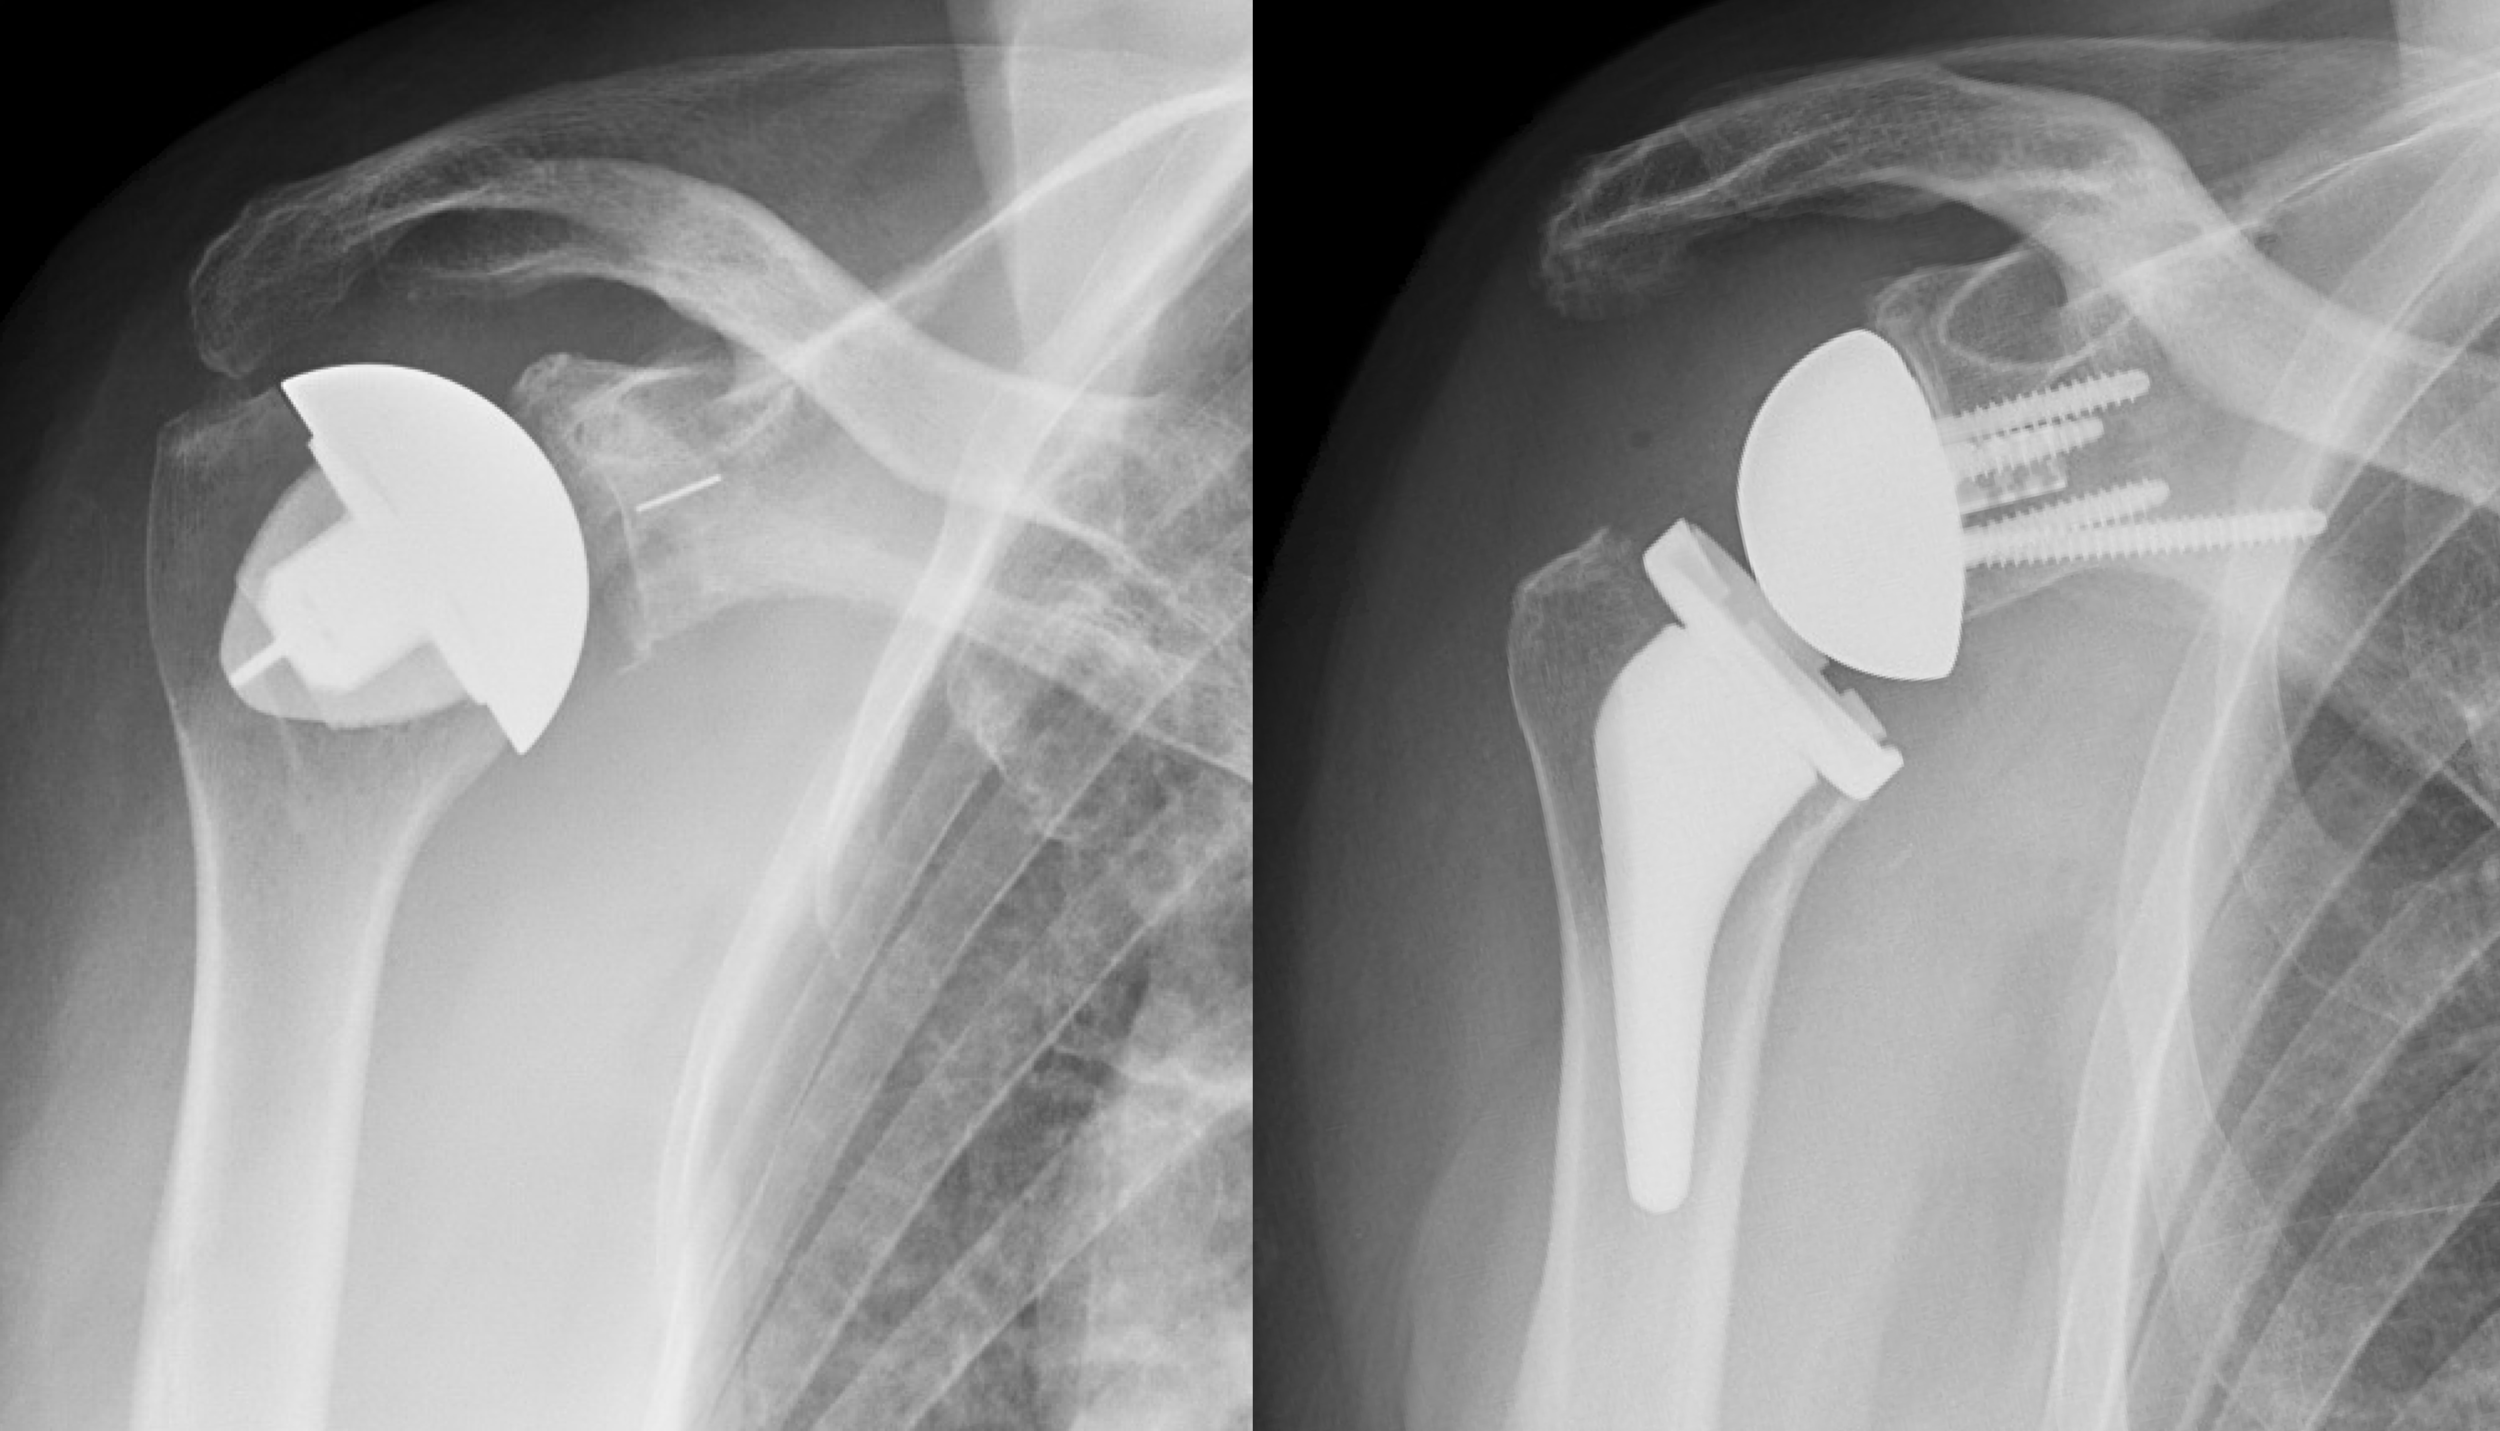

Shoulder Blade Pain: Causes and Effective Treatments

Struggling with persistent right arm pain? Discover the common causes behind aching, numbness, and discomfort in your limb. From rotator cuff injuries and tendonitis to nerve compression, learn how to identify symptoms, explore effective treatment options, and find relief. Get expert insights on when to see a doctor for your arm pain and start your recovery today.